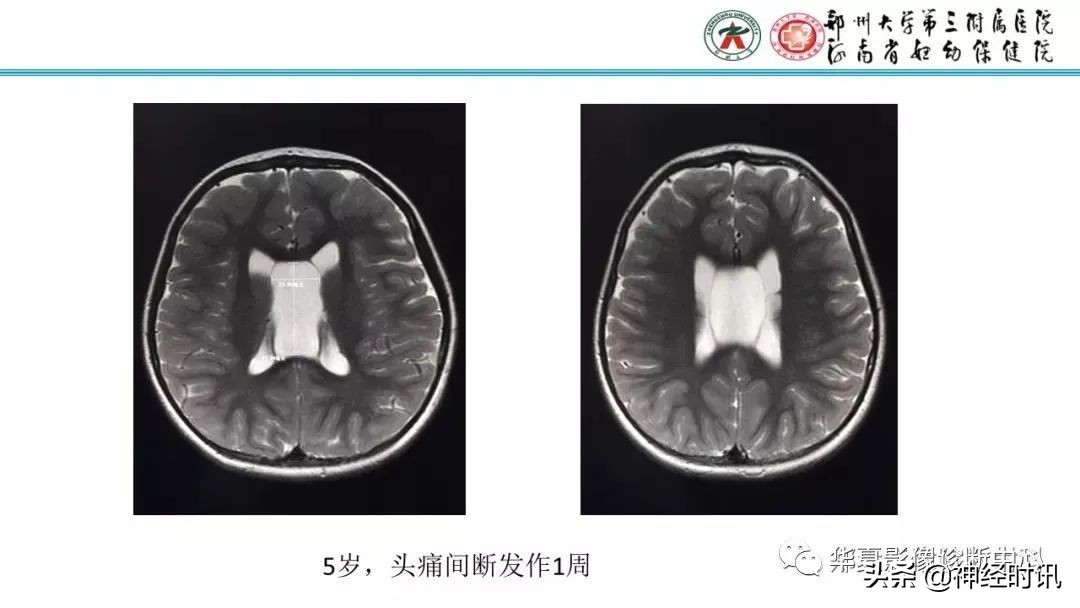

作者:刘真真 郑州大学第三附属医院医学影像科